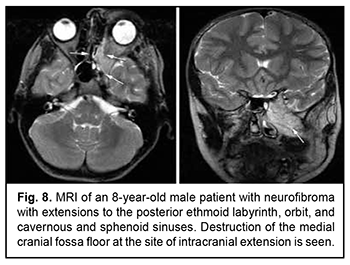

Craniofacial meningioma usually develops due to incompletely removed olfactory fossa meningioma, sphenoid wing meningioma or middle cranial fossa meningioma. A meningioma in any of the above locations, if incompletely removed (particularly, incompletely removed skull base infiltration) may become the origin of the subsequent growth on the inner and outer skull surfaces. We noted intra- and extra-cranial growth of primary meningioma at the ethmoid labyrinth, medial middle cranial fossa and medial posterior cranial fossa. Fig. 6 exemplifies the further spread of the sphenoid wing meningioma to the middle cranial fossa floor, cavernous and sphenoid sinuses, orbit, infratemporal and pterygopalatine fossae, and nasal cavity after incomplete tumor removal. It is noteworthy that, within the field of ophthalmic oncology, sphenoid wing meningiomas constitute a major portion of the large tumors of the anterior skull base and orbit. The tumor extends intracranially and extracranially from the pterygopalatine fossa, leading to destruction of the floor of the medial middle cranial fossa and the involvement of the cavernous sinus (Figs. 7, 8).